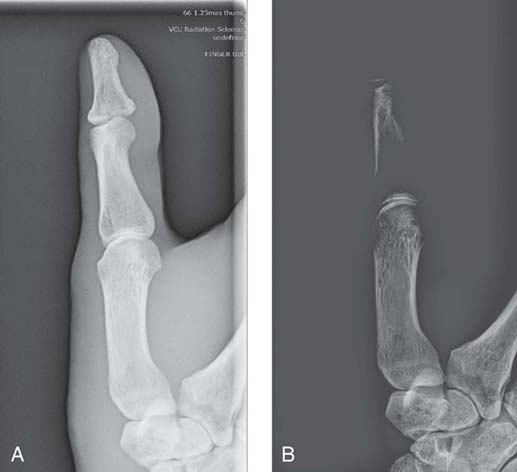

In addition to size distortion, objects that are being imaged can be radiographically misrepresented by distortion of their shape. Shape distortion can radiographically appear in two different ways: elongation or foreshortening. Elongation refers to images of objects that appear longer than the true objects. Foreshortening refers to images that appear shorter than the true objects. Examples of elongation and foreshortening can be seen in Fig. 3-26.

FIG. 3-26 A, No distortion. B, Foreshortened. C, Elongated. (From Mosby's Instructional Radiographic Series: Radiographic Imaging, St. Louis, 1998, Mosby.)

Shape distortion can arise from inaccurate central ray (CR) alignment of the tube, the part being radiographed, or the IR. Any misalignment of the CR among these three factors—tube, part, or IR—alters the shape of the part recorded in the image.

Sometimes shape distortion is advantageous in particular projections or positions. For example, CR angulation is sometimes required to elongate a part so that a particular anatomic structure can be visualized better. Also, rotating the part (and therefore creating shape distortion) is sometimes required to eliminate superimposition of objects that normally obstruct visualization of the area of interest. In general, shape distortion is not a necessary or desirable characteristic of radiographic images.